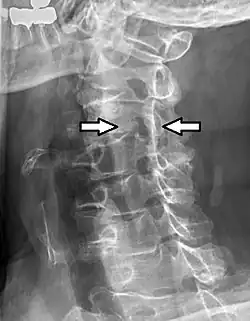

C5-C6, followed by C6-C7, is the most common location for radiculopathy in the neck. | |